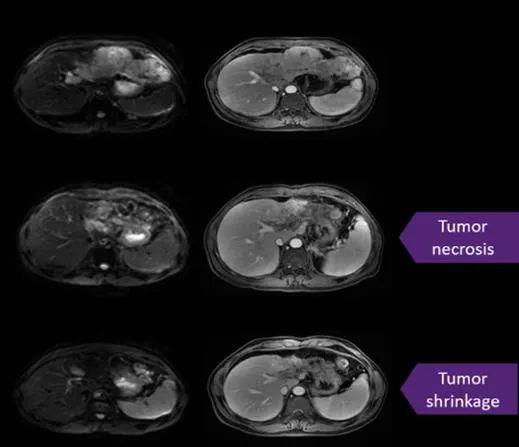

患者13是一名52岁的男性,这是一位病情很重的患者,肝脏多发病灶三年多,期间进行了5种化疗栓塞(TACE)和11次射频消融术的治疗。入组前进行了GPC3IHC染色,结果评分为3+。神奇的是,CART细胞输注后4周开始,MRI显示病变大小明显减少,a和c病变完全消失,b病变从14.2×13.4mm缩小至13.9×13.0mm。截止数据分析时,这名患者还健康的活着。